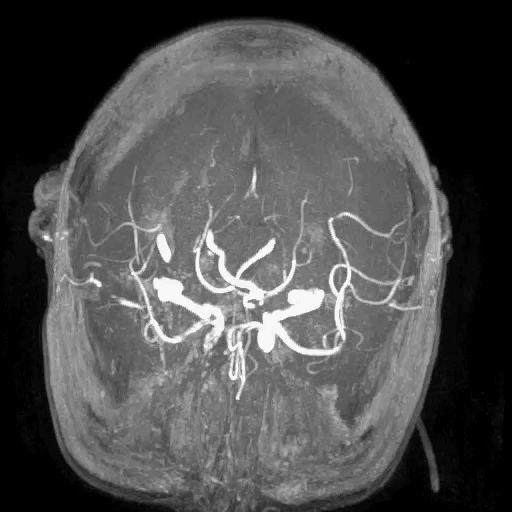

MRA:右侧大脑中动脉闭塞。

脑血管造影:3型主动脉弓,右侧颈内动脉起始段闭塞,后循环及左侧颈内动脉均未向左侧颈内动脉供血区代偿。